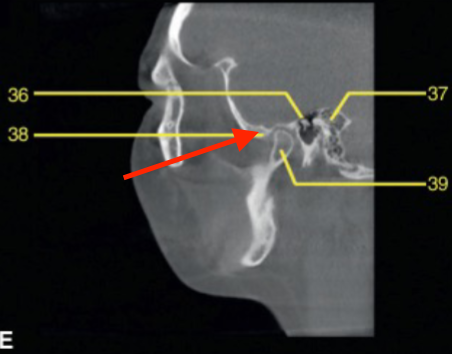

glenoid fossa

identify the structure

articular eminence

styloid process

mastoid process